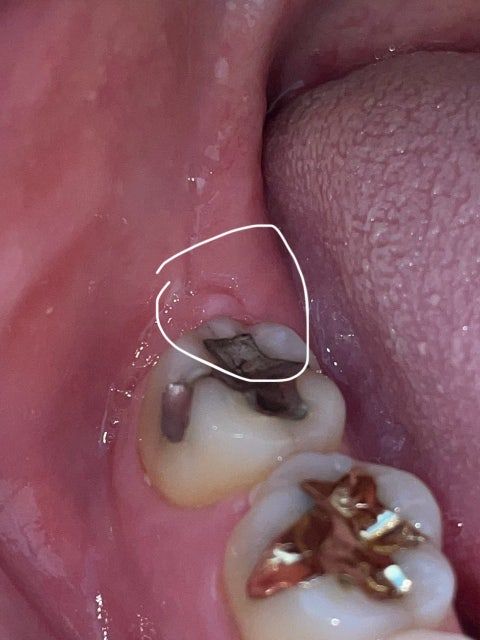

매복 사랑니 발치 후 발치 부위에 이상한 혹이 올라왔어요 이게 어떤 질병인가요?

아래 매복 사랑니를 발치한 부위에 2년 정도 지난 후에 혹 같은 게 올라왔습니다 통증도 있어서 치과에 방문하니 별거 아니라고 하는데.. 저게 원인이 뭐고 어떤 질병인지 궁금합니다

• 1번 째 사진

사랑니 발치 시에 해당 부위가 아물면서 저런 형태로 뭉쳐 나은 것으로 보입니다. 문제가 될 건 없습니다.

사랑니를 발치하고 발치한 부위가 아물면서 혹이 있는 형태로 아물기도 합니다.

염증이 아니라면 크게 문제가 되지는 않기때문에 걱정하지 않으셔도 될것으로 생각됩니다.

큰 문제가 잇는건 아니고 잇몸이 치유되면서 과증식 된상태이니 너무 걱정은 안하셔도 될것같습니다.

특별한 질병이 있거나 한 것은 아니며, 해당부위 잇몸이 차오르면서 볼록하게 조직이 형성된 것으로 보입니다. 통증이나 붓기가 동반되지 않는 경우에는 문제가 되지 않습니다.